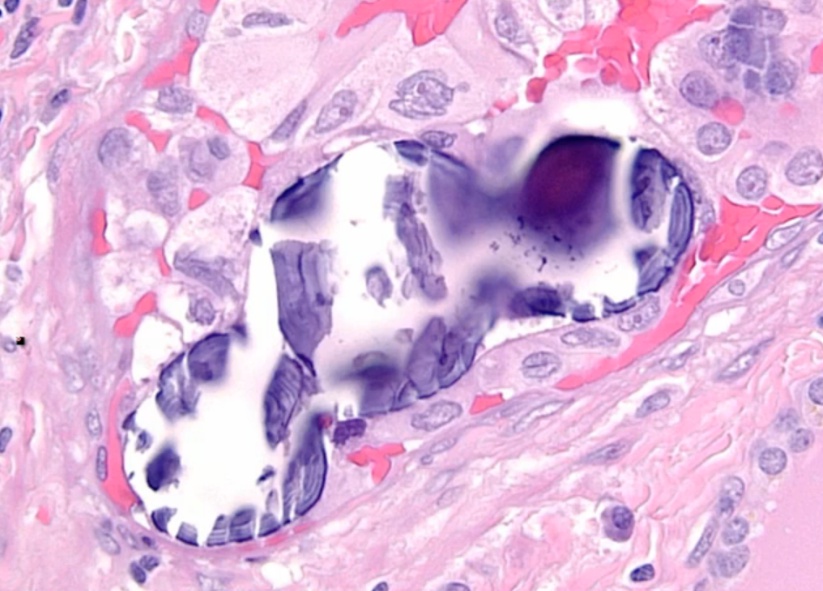

Chronic inflammation, germinal centers and Hurthle cells:

_Because thyroid follicles are normally lined by low cuboidal epithelium, this is also known as Hürthle cell metaplasia.,

_Histologically, defined by:

Lymphocytic infiltrate (germinal centers)

Atrophic thyroid follices lined by Hürthle cells (pink epithelial cells).,